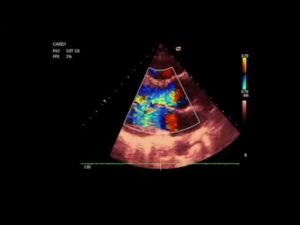

| Эхокардиография |

|

- Нарушение подтверждается на ЭхоКГ. Ультразвуковой метод выявляет увеличение камер сердца и неполное закрытие митрального отверстия.

На ЭхоКГ – утолщение створок клапана, кальциноз, расширение левого предсердия, регургитация митрального клапана III степени.